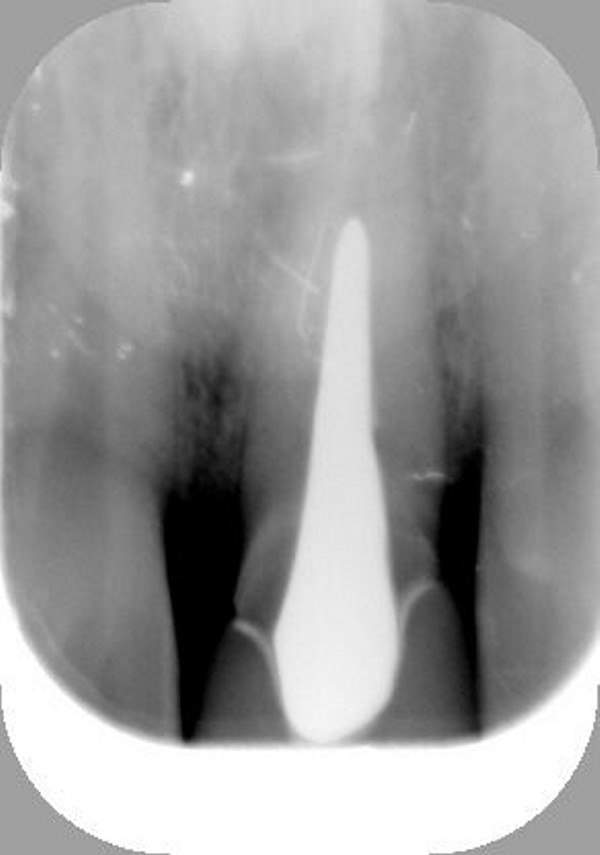

Fig.01(Pie de foto: Fractura de corona)

Fig.03(Pie de foto: Fractura radicular)

Fig.04(Pie de foto: Oclusión Habitual

Fig.05(Pie de foto: Oclusión en Relación Céntrica)